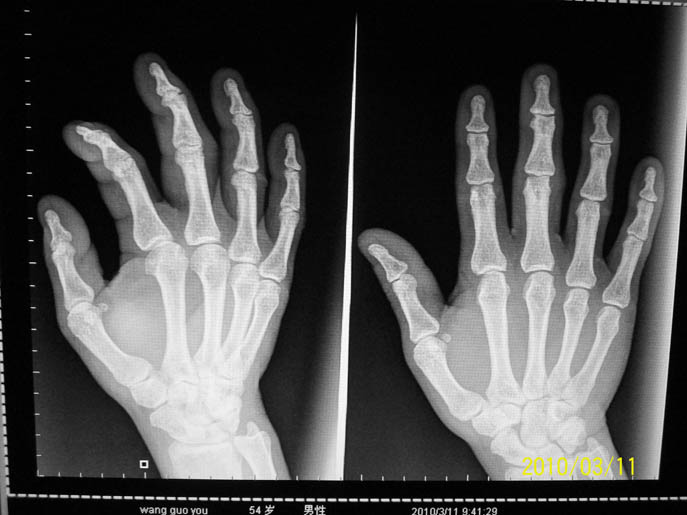

标题: X6969:少见病例,该下何结论?

病人为45岁壮年男子,有长期手工作业史。右手中指近侧指间关节软组织肿胀,并见其内有一点状致密影。

该处指间关节间隙变窄且不等宽,骨质未见明确异常,结合软组织改变,考虑关节囊的慢性炎性病变可能。

骨质未见明显异常,而软组织肿胀,病史提供:有长期手工作业史。考虑劳损退变吧

中心线不在指间关节而在掌指关节,因此对于轻微的指间关节改变不好下结论,但总体看没见明显异常。

诸掌骨、指骨骨质形态、密度未见异常。骨皮质光滑、连续,骨小梁走形自然。指间关节间隙无明显狭窄。

结论:未见异常